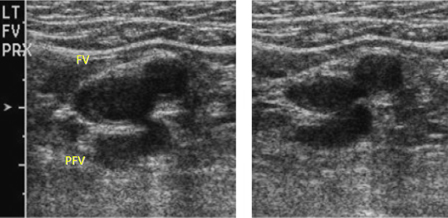

მოკლე ღერძული ულტრაბგერითი გამოკვლევა გვიჩვენებს ბარძაყის ვენასა(FV) და ბარძაყის ღრმა ვენას(PFV) ბარძაყის არტერიასთან ახლოს, კომპრესიამდე(მარცხნივ) და კომპრესიის შემდეგ(მარჯვნივ)

Jeffrey W. Olin -ის კოლექციიდან; გამოყენება ნებადართულია